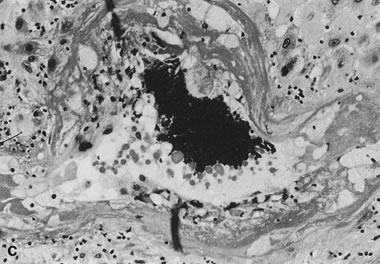

In the basal plate or the placental bed, uteroplacental arteries with absent, incomplete, or failed adaptation have variable persistence of vascular muscle and elastic lamina (Fig. 13). This leads to increased uterine vascular resistance, decreased capacitance, and decreased total blood flow to the placenta. Doppler and isotope studies in the human suggest that uteroplacental flow is decreased to 50% to 70% of normal, which may explain the often associated fetal growth retardation.120,121 Increased uterine artery resistance parallels histologic evidence of impaired trophoblast migration.122 It is been often held that trophoblast invasion of the uteroplacental vasculature is completed at the myometrial level by the middle of the second trimester. Trophoblast vascular conversion at those deeper levels commonly continues even into the early third trimester. Endovascular trophoblast in the superficial (basal plate) uteroplacental arteries later than the early midtrimester may reflect abnormal (delayed) uteroplacental vascular conversion. Fibrinoid necrosis of the vessel wall with mural foamy cells (“atherosis,” see Fig. 13) is accompanied by dense lipoprotein(a) deposition within the vascular wall, reflecting a vascular pathology similar to atherosclerosis. Other common uteroplacental arterial lesions are thrombosis and chronic vasculitis. For cases of preeclampsia in which uteroplacental vascular pathology is common, Redline and Patterson123 explored the hypothesis that there is a generalized maturation defect in the extravillous trophoblast that leads to increased accumulation of trophoblast in the superficial layers of the implantation site. Increased thickness of basal cytotrophoblast and increased cytotrophoblast proliferation (marked by immunostaining with proliferating cell nuclear antigen) were seen in preeclamptic placentas 24 to 40 weeks of age compared to term. Whether trophoblast “pile-up” at the placental/decidual interface reflects an intrinsic invasive defect, or whether their migration is inhibited by maternal factors is not clear. This pile-up is not, in our view, specific to preeclampsia. It is, however, yet another marker of abnormal uteroplacental interaction assessable in the delivered placenta.

Fig. 13. A. Normally adapted maternal spiral arteries with trophoblasts within the vessel lumen and invading the wall, seen at the end of the second trimester (hematoxylin and eosin, ×10). B. A vessel with failed adaptation, with retained smooth muscle, seen near term (hematoxylin and eosin, ×10). C. Acute atheroma with intimal and medial proliferation, fibrinoid necrosis, foamy macrophages, and increased numbers of lymphocytes (“chronic vasculitis”) from an early third-trimester placenta from a woman with pregnancy-induced hypertension (hematoxylin and eosin, ×20).